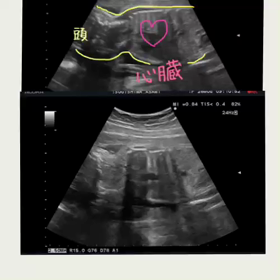

予定日まであと98日

2017年6月16日